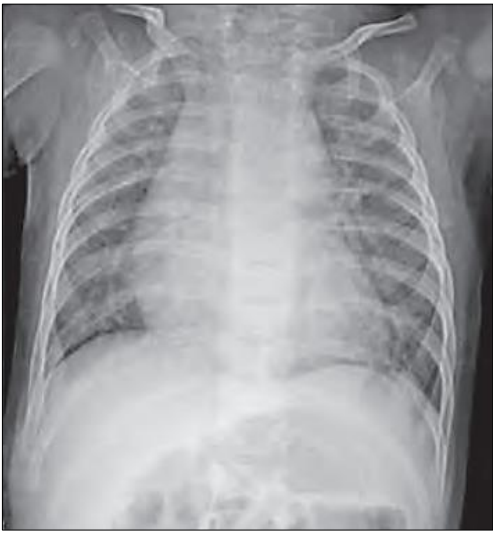

Lactente, dois anos, previamente hígido, iniciou febre há três dias, associado há tosse e coriza; há um dia, o responsável notou que o menor está mais cansado e com piora da prostração, o que motivou ida ao pronto-socorro infantil. Em exame físico: ausculta respiratória com estertores crepitantes bilaterais, tiragem, taquipneia (FR: 60 irpm) e tiragem subcostal. Assinale a conduta adequada para este paciente.